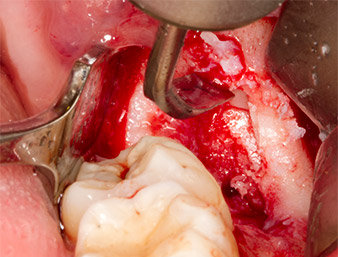

Um autogenes Material für die spätere Wundversorgung zu gewinnen, wurden mit einem piezochirugischen Instrument (Piezomed B5) gesunde Knochenspäne aus der Umgebung des Wurzelrests gewonnen (Abb. 5).

Piezomed B5

Abb. 5: Mit einem meißelförmigen piezochirurgischen Instrument (Piezomed B5) wird Knochen im Bereich der Alveole abgehoben. Dieser dient nach Entfernung des Wurzelrests als autologes Augmentationsmaterial

(vgl. Abb. 13 und 14).

Das autogene Gewebe wurde mit dem schaufelförmigen Arbeitsteil des Instruments entnommen und bis zur weiteren Verwendung in physiologischer Kochsalzlösung aufbewahrt (vgl. Abb. 13).